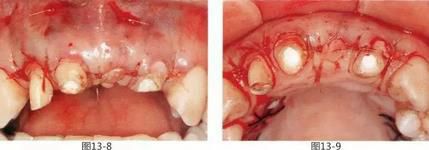

圖15-1  初診時,右上1缺失部的橋體下方牙根部使用義齒專用樹脂,提高了橋冠的美觀性以后的正面照。

圖15-2  拆除后的橋冠的舌側面。橋體內面沉積大量牙結石。